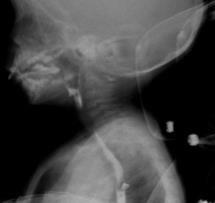

Videofluoroscopy

ORAL PREPARATORY PHASE IN EATING SOLID FOOD

✓ Loss of food out mouth, pushed out with tounge

✓ Food in anterior sulcus

✓ Limited tongue movement

✓ Problem about turning the food into bolus formation

✓ Food in valleculae and pharynx,

pre swallow

✓ Jaw grading inappropriate

ORAL PREPARATORY PHASE IN DRINKING LIQUID FOOD

✓ Loss of food out mouth

✓ Liquid in anterior sulcus

✓ Food pushed out with tounge

✓ Food in valleculae and pharynx, pre swallow

ORAL PROPULSIVE. PHASE:

✓ Food or liquid remains in anterior and/or lateral sulcus

✓ Food or liquid remains on floor of mouth

✓ Limited posterior tongue movement

✓ Reduced base of tongue action

✓ Tongue-soft palate contact incomplete

✓ Multiple swallows per bolus

✓ Delayed oral transit time

PHARYNGEAL PHASE

✓ Nasopharyngeal regurgitation

✓ Slow bolus passage through Pharynx

✓ Reduced pharyngeal contraction/motility

✓ Residue cleared with next swallow

✓ Residue not cleared

✓ Reduced hyolaryngeal execursion

✓ Penetration to underside of epiglottis

✓ Penetration to laryngeal vestibule

✓ Aspiration before, during and after swallow

✓ Aspiration respons: not effective cough, no cough – silent aspiration

ESOPHAGEAL PHASE

✓ Slow bolus passage through UES

✓ Residual on UES

✓ Cricopharyngeal dysfunction

✓ Slow bolus passage through esophagus